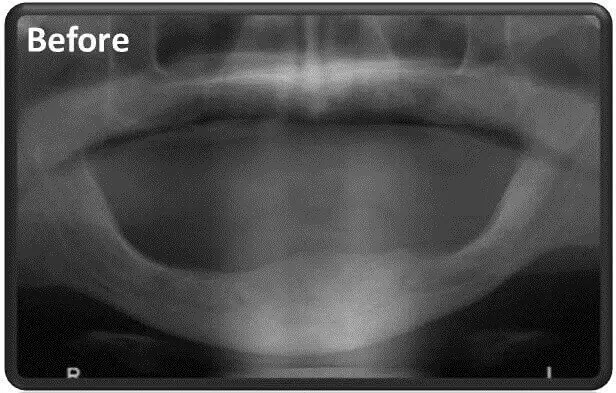

When there is deficiency of the jawbone, there is a problem – the natural position for anchoring the dental implants is damaged and the dentist is required to find a solution to overcome this problem. Here we have to distinguish between a condition of bone loss in the lower jaw and a lack of bone in the upper jaw, when each of these medical conditions has a different dental solution.

In cases where there is lower jaw deficiency The Dentist can use a variety of the following techniques:

When there is lower jaw deficiency the standard dental implant solution isn’t possible in areas of bone deficiency. As such, in these areas unique implants are used called Plate Implants, or Basal Implants. These aren’t screwed into the bone, rather the implants are attached to the jaw but on the sides of the gums.

in cases where there is lower jaw deficiency, it often happens that the gum ridge collapses and needs to be lifted back into place in order to restore the smile line. In such a case, we look for a placement that is hard enough to anchor the implants. Thickening the bone is an option or using the rigid nerve canals are also options for anchoring the dental implants. However then we are risking harming the nerve that passes through this canals. Therefore, we use a unique technique that moved the nerve aside until the completion of rehabilitation and anchoring of the dental implants, then move them back into place intact.